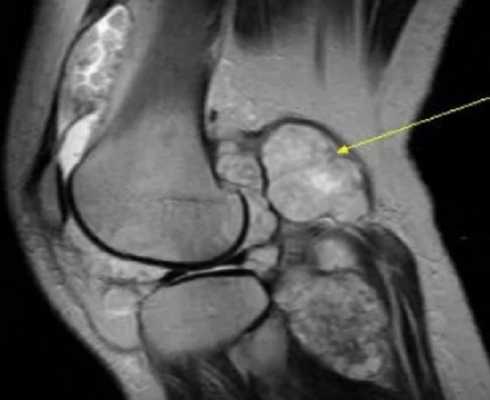

Синовиальная саркома на МР-скане (стрелка)

- Добро-, злокачественные новообразования костей, суставов, мягких тканей. К основным первичным малигнизирующим остеогенным опухолям коленного сочленения относят фибросаркому, саркому. Вторичные новообразования метастазируют из других органов, чаще из легкого и молочной железы. Сустав за счет отека увеличивается в объеме, присутствуют усиление сосудистого рисунка, местное повышение температуры, атрофия мышц ниже уровня поражения. Опухоль может брать начало в хряще, костном мозге, сосудах, соединительных тканях. Доброкачественные новообразования - фиброма, липома, гемангиома, остеохондрома и пр. Окончательная верификация подразумевает морфологическое изучение биоматериала. МРТ коленного сустава позволяет предположить характер патологии.